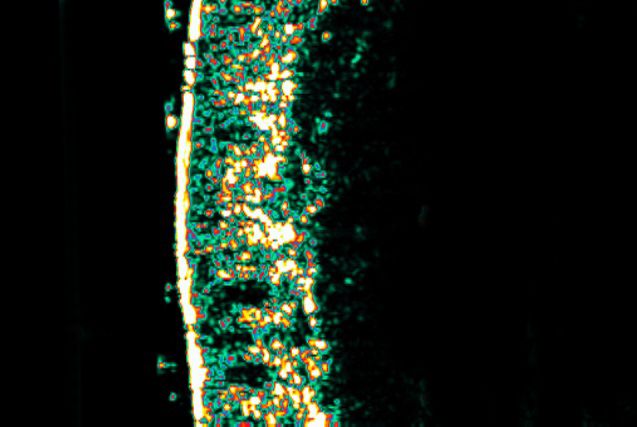

Dopo 30 giorni di trattamento; l’analisi mostra una produzione significativa di collagene.

30%

Aumento di oltre il 30% di produzione di collagene

19.6%

Aumento di oltre il 19,6% di elasticità cutanea

11.6%

Riduzione di oltre l’11,6% della visibilità delle rughe

11.1%

Aumento di oltre l’11,1% di luminosità della pelle